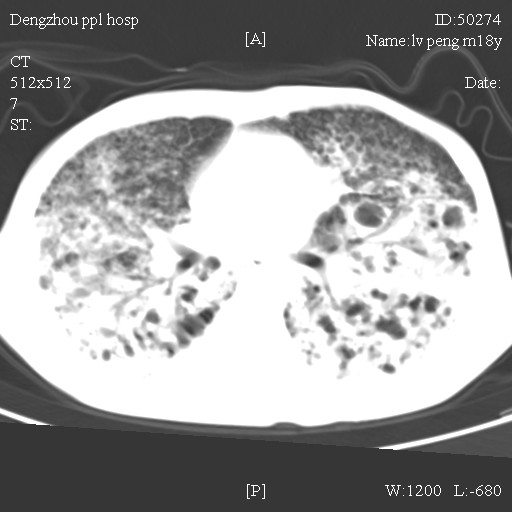

标题: CT10510:男.18岁,咳嗽咳痰两月.(有病理) [打印本页]

标题: CT10510:男.18岁,咳嗽咳痰两月.(有病理)

双肺布满大片状实变及网格状结节影,内参杂大小不等的气囊及空气支气管征,心脏增大。考虑:1 全身结缔组织疾病—系统性红斑狼仓?2 肺泡蛋白沉积症合并感染!

双肺布满大片状实变及网格状结节影,内参杂大小不等的气囊及空气支气管征,双侧胸膜腔少量积液,双下肺近膈面透亮度尚可,病人较年轻,病变较重(不知为什么上胃管?)考虑:1.胶原病肺部改变,2.组织细胞病x。结合实验室检查。

首先考虑组织细胞x病。两肺中上肺野多发囊腔,中下肺野内见多发小结节,并可见肺间质增厚。患者是男性,年龄较小。胶原性病变比较多见的类风湿、系统性红斑狼疮和硬皮病临床和影像均不是很支持,类风湿和系统性红斑狼疮的肺部表现最常见的是胸腔积液,硬皮病可见食管的扩张。

肺内多发斑片状、结节状、融合大片状及网格状影,多发薄壁空腔影,胸膜肥厚,纵隔、气管右移,考虑ⅲ型肺结核,多发空洞,继发肺间质纤维化。

双肺结核并播散.患者以肠梗阻入院,手术为肠结核.术后咳嗽做ct检查.